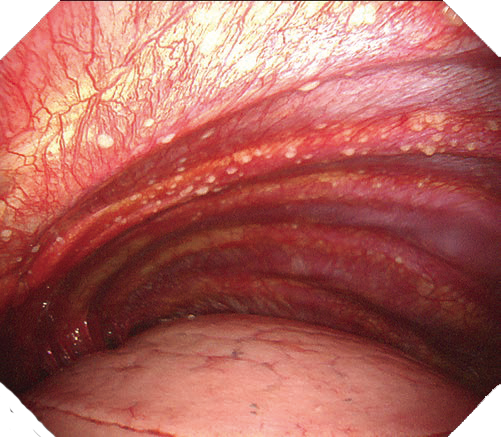

明るく鮮明なハイビジョン画質

高精細なハイビジョン画質により胸腔内の観察、診断、処置をサポートします。